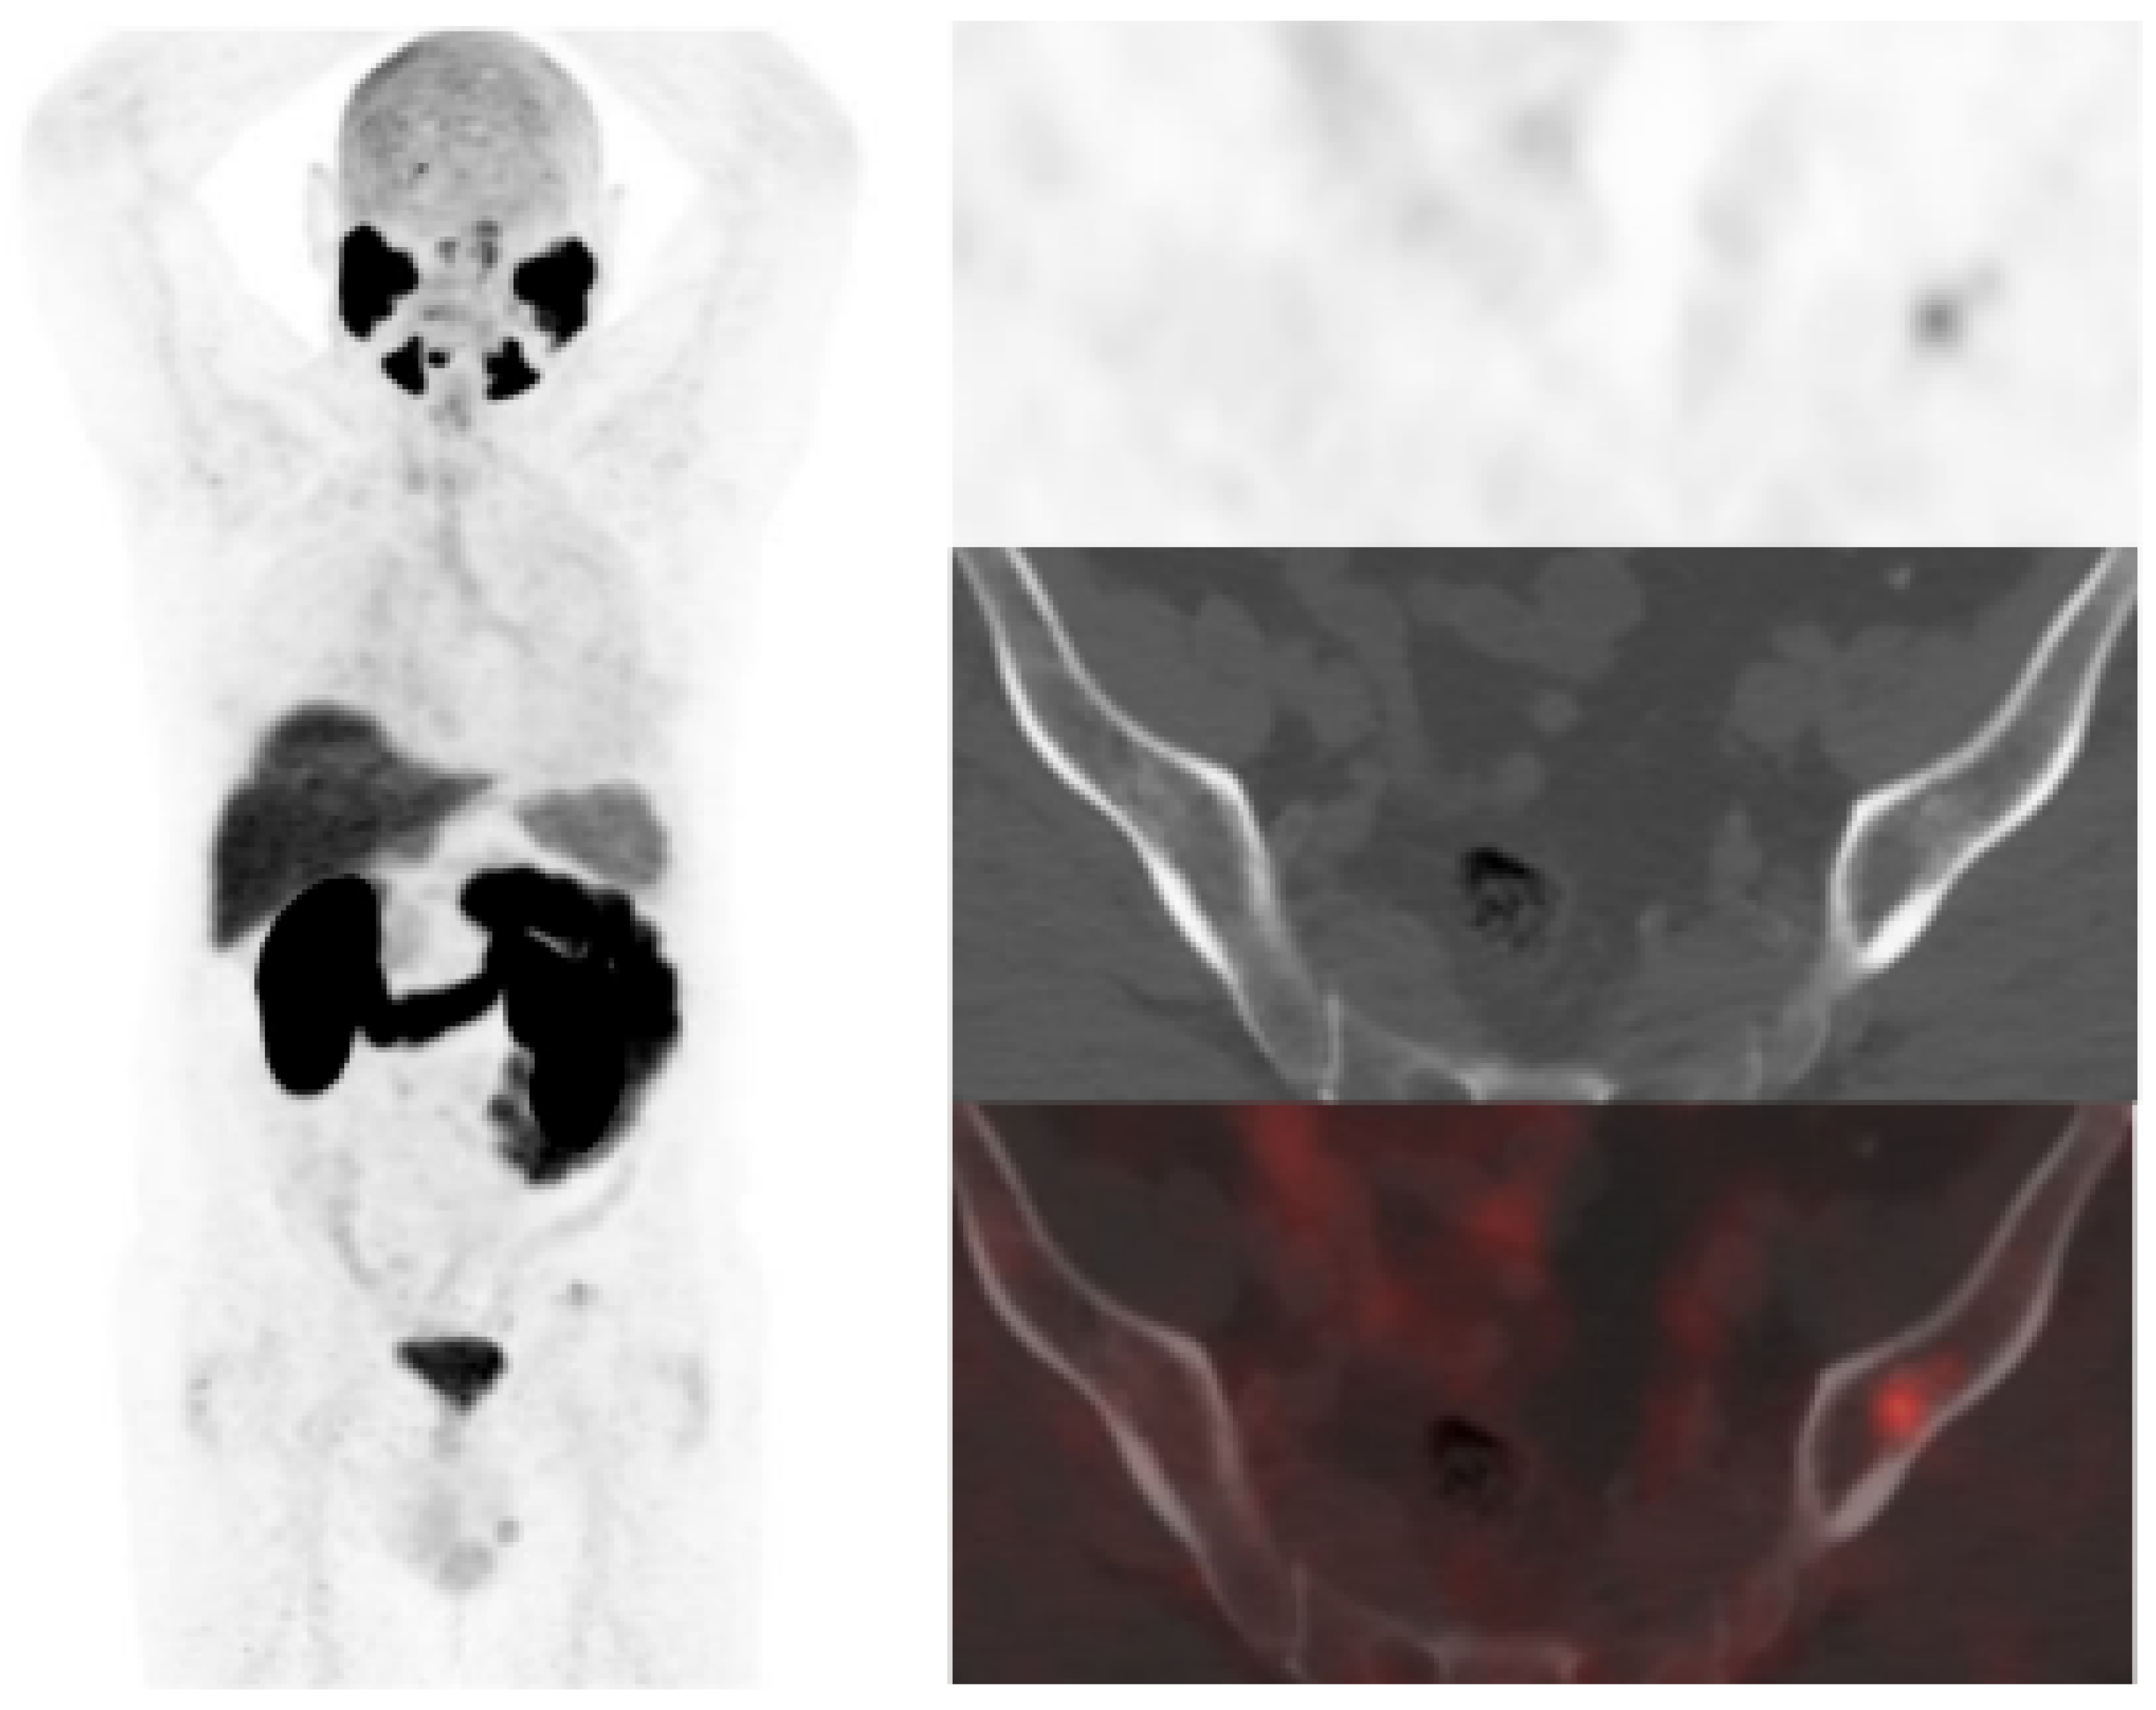

[18F]DCFPyL showed a higher DR than [18F]F-choline, 64.5% (89/138) and 33.3% (46/138), respectively. Both scans were negative in 44 patients (31.9%) and positive in 41 (29.7%). However, in 20/41 patients, [18F]DCFPyL visualized additional lesions compared with [18F]F-choline, which entailed miTNM stage change in 17 patients (Figure 1).

Figure 1.

59-year-old patient. Gleason 7 PCa treated with radiotherapy plus ADT. After ADT withdrawal BCR was detected (PSA 2.44 ng/mL, PSAdt 2.6 months, PSAvel 0.15 ng/mL/month). [18F]F-choline (a) demonstrated only prostatic uptake (white arrow) and [18F]DCFPyL-PET/CT (b) showed prostatic tracer uptake and lymph nodes metastases (white and black arrows). Time window of sixteen days between both scans. [18F]DCFPyL changed therapeutic management allowing escalation (ADT + Apalutamide).